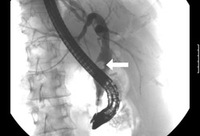

Colangitis aguda

Colangiopancreatografía retrógrada endoscópica que muestra un cálculo de gran tamaño (flecha) en la sección media del conducto biliar común (CBC)

De la colección de Douglas G. Adler; usado con autorización